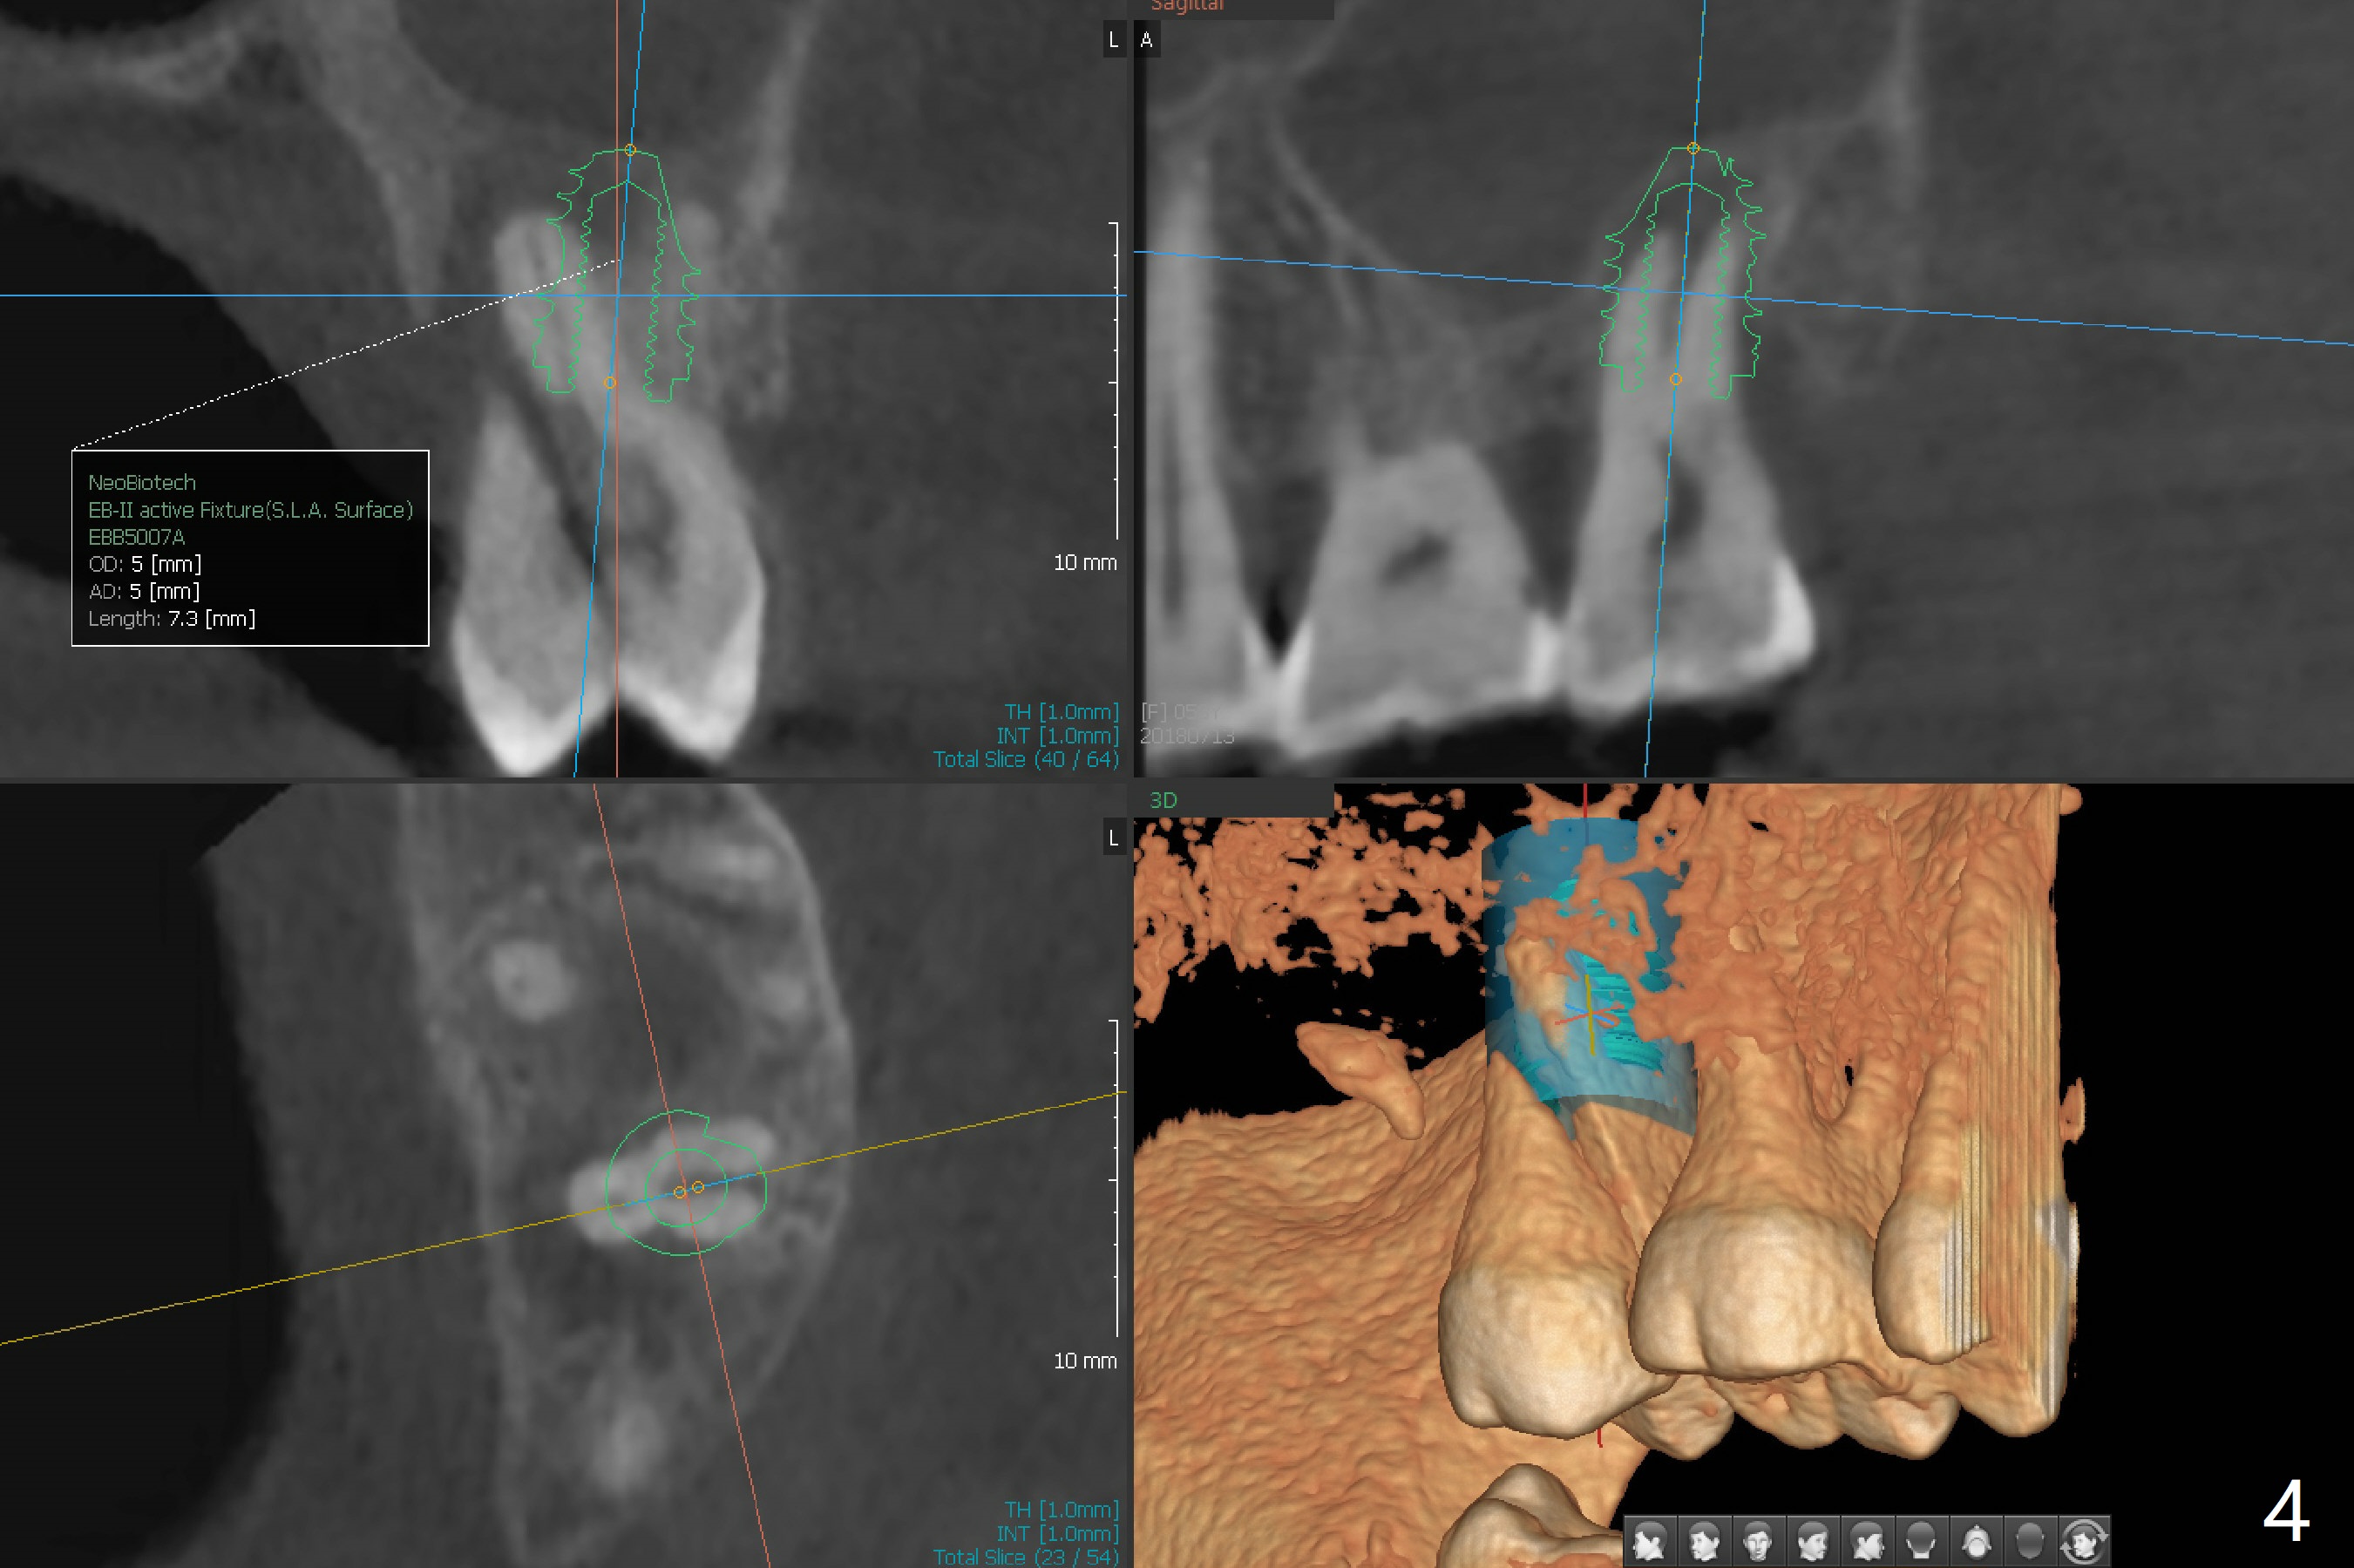

While the tooth #2 has a mesiodistal crack line with symptom (Fig.1 arrowheads, crown pending), the tooth #15 has a mesiodistal fracture (Fig.2). Immediately preop 5x5 cm CBCT (Fig.3) confirms the palatal (P) fracture with palatal bone loss. Although a 5x7.3 mm implant fits the site by design (Fig.4), a much longer implant is required to achieve primary stability past the sinus floor using IBS Magic Expanders (Fig.5,6 (20-30 Ncm; sinus lift with PRF membrane and allograft)). In contrast, primary stability could not be obtained by engaging dummy implant to the socket walls. A short implant without sinus lift is associated with less obvious complication such as fibrointegration. The implant seems osteointegrated 4.5 months postop (Fig.7). The abutment is changed to 6.5x4(5) mm before impression. There is no bone loss 5 months post cementation (Fig.8 (11 months postop)). It is the same 2.5 years post cementation (Fig.9,10).